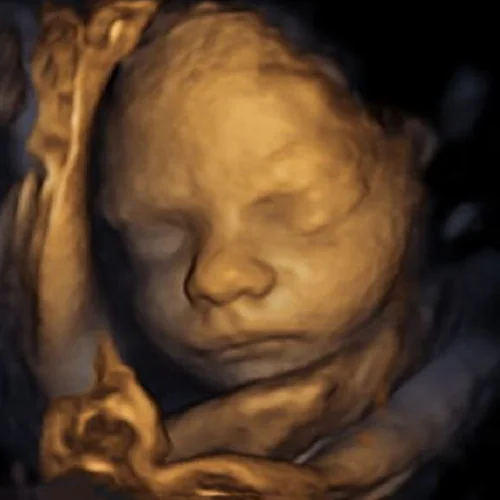

. Hair makes different echo patterns from fluid and other soft tissues so this is. By the 15th week your babys hair pattern starts to develop as the hair pushes through the scalp. 3d ultrasound is a medical ultrasound technique often used in foetal cardiac trans-rectal and intra-vascular applications.

Around this time the fuzzy halo of hair will be visible on ultrasounds. EP 9 Our First 3D Ultrasound Booking Our Baby Shower. Unfortunately 3D4D ultrasound technology cannot see any hair on the baby however standard 2d black and white ultrasound can usually pick up strands of hair.

Unfortunately 3D4D ultrasound technology cannot see any hair on the baby however standard 2d black and white ultrasound can usually pick up strands of hair. It is possible to see hair in a 2D ultrasound but not in a 3D one. Hair follicles start to form deep in your babys skin by 14 weeks of pregnancy.

According to medical experts the best method for determining if the baby has hair is to use a traditional 2D ultrasound black and white which displays fuzz an indicator that. 2D ultrasounds are the only ultrasounds that are able to pick up individual strands of hair. The shadows are not hair just places it wasnt focused on picking anything.